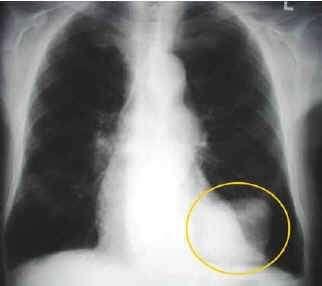

Mówi się o tym, że papierosy szkodzą zdrowiu i działają destrukcyjnie na układ oddechowy żywego organizmu. Jednak nikt głośno nie mówi o wpływie spalin samochodowych na płuca ludzi i zwierząt. A przecież substancje, które wydostają się z rur wydechowych samochodów stanowią mieszaninę gazów i cząstek stałych, które w wysokim stężeniu w bardzo krótkim czasie potrafiłyby zabić dziesiątki organizmów żywych.

Dwutlenek węgla (CO2), tlenek węgla (CO), tlenki siarki (SO2, SO3), tlenki azotu (NOx), węglowodory (HC), pyły, związki ołowiu i innych metali ciężkich – wszystkie te substancje nieustannie krążą w powietrzu wdychanym i wydychanym przez człowieka. Zakładając, że organizm ludzki wdycha powietrze średnio 15 - 25 razy w ciągu minuty (rzadziej w czasie snu, częściej podczas marszu i wysiłku fizycznego), okaże się, że przez płuca człowieka w ciągu dnia przepływają setki litrów powietrza, w którym zawieszone są najróżniejsze toksyczne związki chemiczne. W dużych aglomeracjach, w których auta stoją w gigantycznych korkach i toczą się z prędkościami rzędu 15 – 30 km/h stężenie tych trujących związków bywa jeszcze wyższe (nawet 30 – 40-krotnie). Przenikające do ustroju toksyny bardzo często zostają zdeponowane w komórkach pęcherzyków płucnych, lub z krwioobiegiem dostają się do wszystkich komórek naszego organizmu. Tym sposobem związki ołowiu, benzen i inne toksyczne związki węgla i wodoru zawieszone w powietrzu ostatecznie kończą swoją wędrówkę np.: w… komórkach mięśniowych naszego organizmu! Jak szkodliwe są to substancje, wystarczy wspomnieć tylko o kilku: tlenek węgla, tlenki azotu, węglowodory aromatyczne, w tym benzen,

W ciągu ostatnich kilkudziesięciu lat liczba osób cierpiących z powodu chorób układu oddechowego (astma, zapalenie błon śluzowych, nowotwory) alergii, chorób układu nerwowego (bezsenność, nadpobudliwość, bóle głowy), zaburzeń w funkcjonowaniu układu krążenia znacząco wzrosła. Miliony osób rocznie dowiadują się o tym, że w ich ciałach rozwinął się nowotwór, z którym współczesna medycyna we wczesnej fazie rozwoju na szczęście potrafi sobie radzić. Jednak pytanie brzmi – dlaczego ten nowotwór się rozwinął? W przypadku palacza odpowiedź jest prosta – zawsze można zrzucić odpowiedzialność na papierosa. A co w przypadku osób, które ani nie palą, ani nigdy nie paliły?